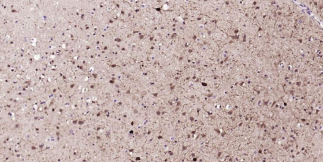

Immunohistochemical analysis of paraffin embedded human brain tissue slide using IHC0378H (Human Parvalbumin Kit).